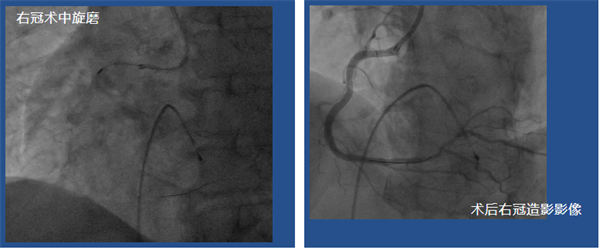

鄭廣生團隊經過對手術難點的分析提出了相應的手術策略順利為患者實施了手術:患者73歲高齡,冠脈多支嚴重鈣化狹窄,存在左主干病變,右冠重度鈣化,需要主動行冠脈旋磨治療,經充分處理右冠病變后,于右冠植入支架3枚。術后患者的胸悶、氣短癥狀明顯緩解,已于近日康復出院。

術后右冠造影影像